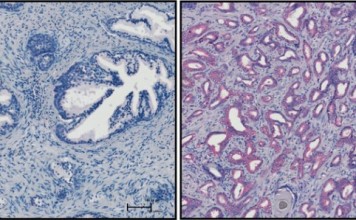

Ученые нашли способ избегать аллергию на молекулярном уровне

В настоящее время в мире проживают миллионы людей с аллергией хотя-бы на одно вещество. Так или иначе, но даже широчайши...